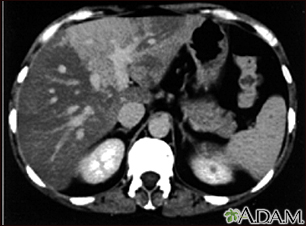

Liver with disproportional fattening - CT scanBackLiver with disproportional fattening - CT scanA CT scan of the upper abdomen showing disproportional steatosis (fattening) of the liver. E-mail FormEmail ResultsName:Email address:Recipients Name:Recipients address:Message: